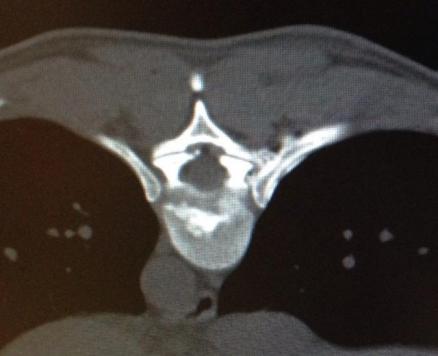

In lokaler Betäubung wird eine Laserfaser durch eine Punktionskanüle in die betroffene Bandscheibe eingeführt. Unter kontinuierlicher Röntgenkontrolle wird die Nadel millimetergenau platziert. Das Verfahren zählt zur Mikrotherapie und beruht auf der Schrumpfung von Bandscheibengewebe durch Hitze. Der innere Kern der Bandscheibe, der Nucleus pulposus, wird dabei schonend verkleinert. Ein Bandscheibenvorfall kann sich dadurch schneller zurückziehen. Es erfolgt eine rasche räumliche Entlastung der bedrängten Nervenwurzel. Weiterhin führt die Hitze zu einer Verödung der Schmerznerven, welche die Bandscheibe umgeben.

Der Eingriff dauert etwa 15 Minuten und wird in örtlicher Betäubung und leichter Sedierung durchgeführt.